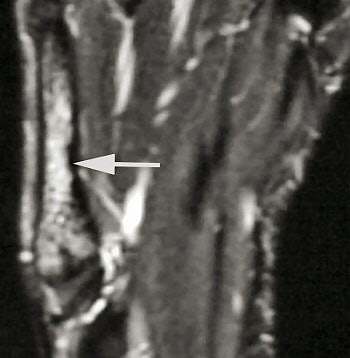

| Short axis image shows bone marrow edema at the base of the third metatarsal. |

The follow-up study was led by Dr. Nancy Major, associate professor of radiology at Duke University Medical Center's musculoskeletal division. Her study determined that MRI can effectively predict metatarsal stress fractures by depicting bone marrow edema (a precursor to fractures), thereby enabling the prevention of potential fractures with the use of orthotics.

In this study, 26 male basketball players from Duke and North Carolina Central University in Durham were imaged before and after their 2003 season. Although 19 of 52 feet showed abnormalities with MRI, only one player had complaints of a symptomatic midfoot. The use of an orthotic provided immediate relief, and the player did not subsequently develop stress fractures.

A player experiencing no symptoms, however, did develop a metatarsal stress fracture before he could be fitted for an orthotic ("The role of imaging in the feet in asymptomatic collegiate basketball players," RSNA meeting, December 2, 2004).